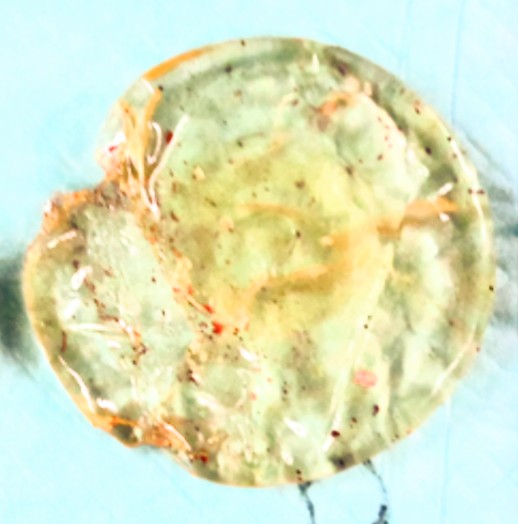

■ 実際に抜去した豊胸バッグ(症例写真)

以下は、拘縮や石灰化が進行したケースで実際に取り出したシリコンバッグ2例です。胸の中でどのような変化が起きているかがわかります。

【症例写真①】被膜や石灰化が付着した豊胸シリコンバッグ。長期間の留置によって内部で変化が進行した状態です。

【症例写真②】石灰化や被膜が付着したシリコンバッグ。内部でさまざまな変化が生じていることがわかる症例です。

こうした変化は、長期間バッグを入れている方では珍しくありません。

抜去の重要性を理解するうえで、参考になる症例です。